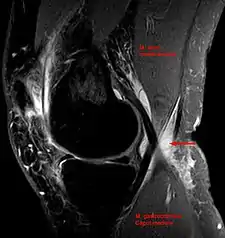

Baker's cyst on MRI, sagittal image